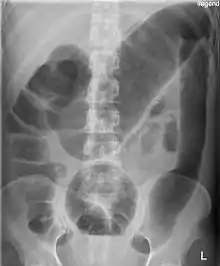

قد تكون هناك علامات الصدمة الإنتانية. يكشف الفحص البدني مضض البطن وانعدام أصوات الأمعاء. يُظهر التصوير الشعاعي للبطن تمدد القولون. وعادةً ما تكون خلايا الدم البيضاء مرتفعة. وقد يكون الإنتان مصحوبًا بانخفاض درجة حرارة الجسم أو نقص الكريات البيض.